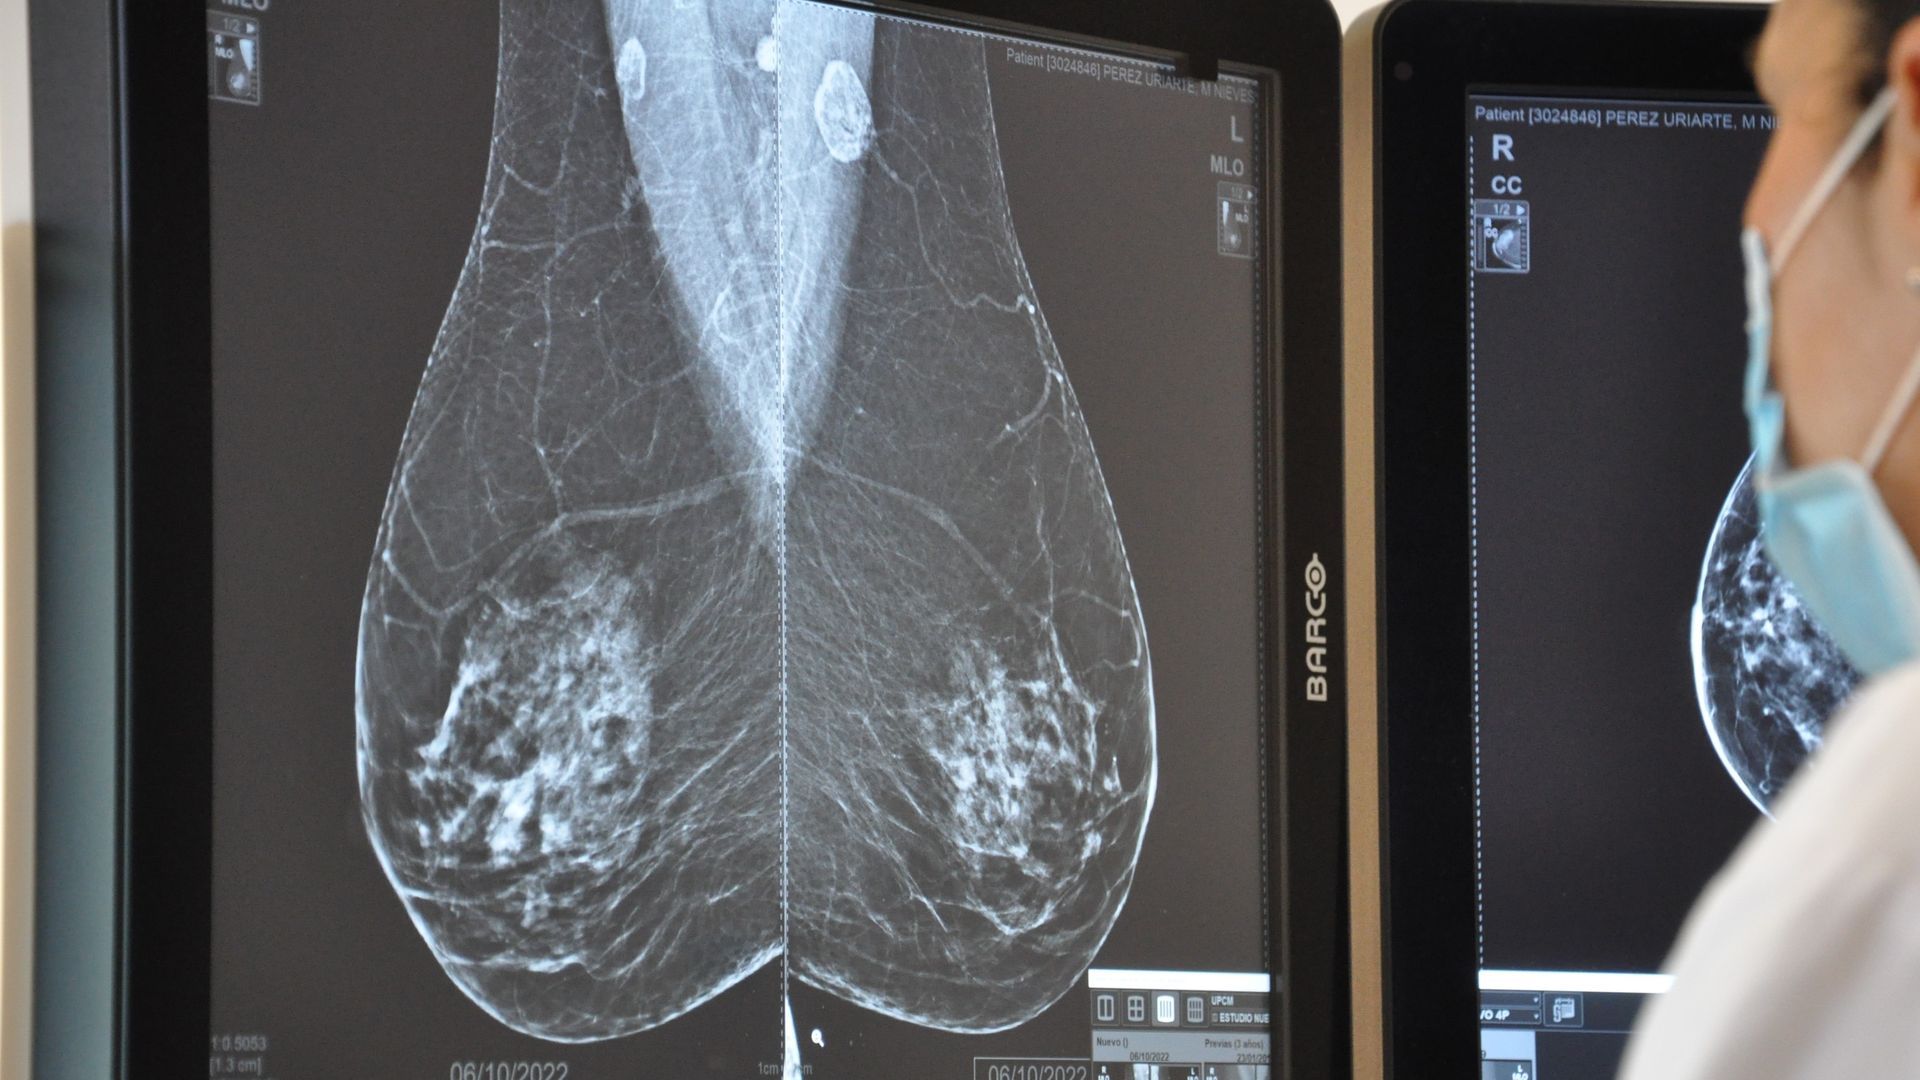

Un médico anuncia un nuevo tipo de mamografía sin dolor ni radiación: "Abraza la mama y crea una imagen en 3D"